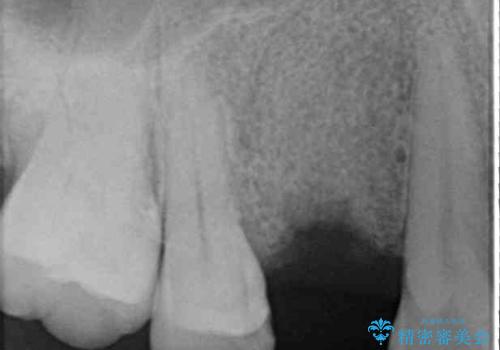

むし歯により歯冠が崩壊してから長いこと経過しているとのことで、歯を失ったことによる他の歯への影響はあまりないと判断されたため、審美領域である上顎前歯部のみにインプラント補綴治療を行うこととしました。

2本の歯が前後に重なった状態でむし歯となっていたので、抜歯後に歯肉や骨の状態が落ち着くのを待ち、インプラントを埋入することとしました。